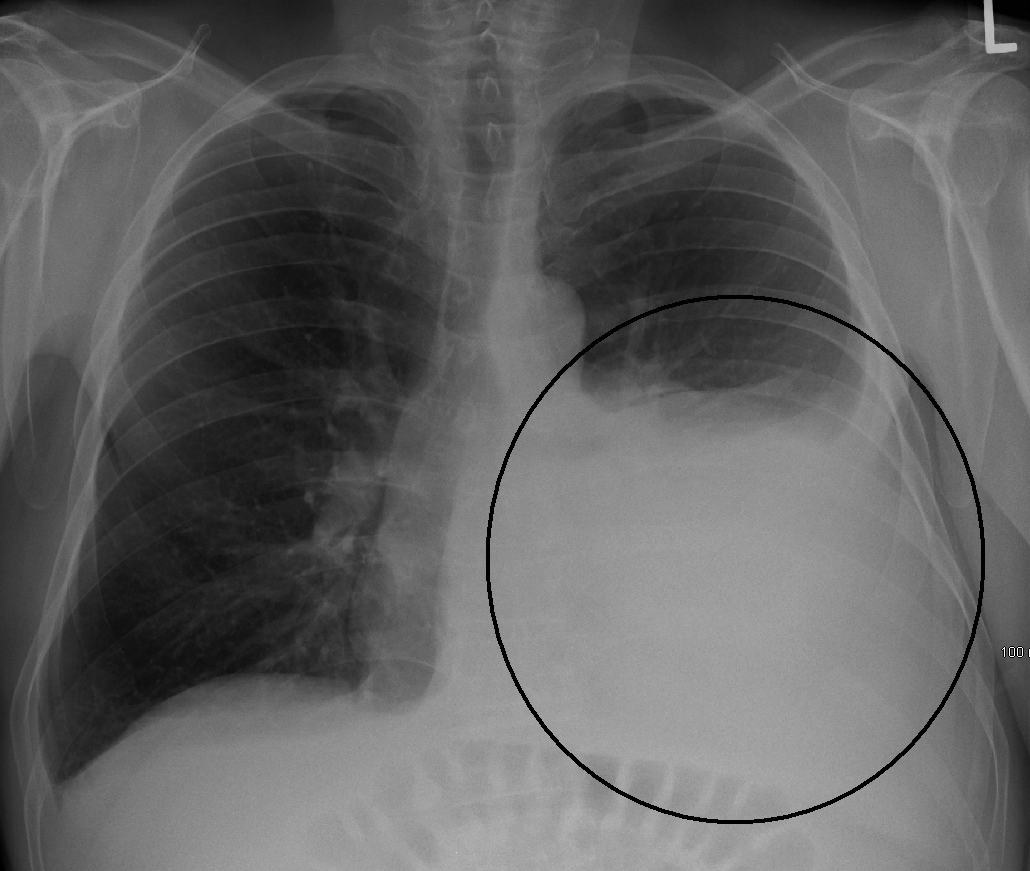

흉막 삼출액은 일반적으로 병력과 신체 검사를 바탕으로 진단되며, 흉부 엑스선으로 확인된다.[13] 흉수는 일반적인 후전방 흉부 X-레이에서 하얗게 보이는 영역으로 나타난다.[14] 흉수는 폐의 나머지 부분보다 밀도가 높기 때문에 흉강의 하단 부분으로 중력에 의해 이동한다. 흉수는 폐와 흉벽에 의해 결정되는 흉막 공간의 모양에 따라 기본적인 유체 역학에 따라 움직인다. 흉막 공간에 공기와 액체가 모두 포함되어 있으면 폐 공간에 맞춰지지 않고 수평적인 공기-액체 경계면이 나타난다.[15] 측면 decubitus(환자가 흉수가 있는 쪽으로 누운 상태) 자세의 흉부 방사선 사진은 더 민감하며 50mL의 액체도 감지할 수 있다. 기립 흉부 X-레이가 흉수를 감지하려면 250~600mL의 액체가 있어야 한다(예: 둔화된 늑골횡격막각).[16]

흉부 컴퓨터 단층 촬영은 진단에 더 정확하며 흉수의 존재, 크기 및 특성을 더 잘 특성화하기 위해 얻을 수 있다. 폐 초음파는 CT와 거의 동일한 정확도를 가지며 흉부 X-레이보다 더 정확하며, 흉수를 진단하기 위해 환자 곁에서 점점 더 많이 사용되고 있으며 안전하고 역동적이며 반복 가능한 영상 촬영 방식을 갖는다는 장점이 있다.[17]